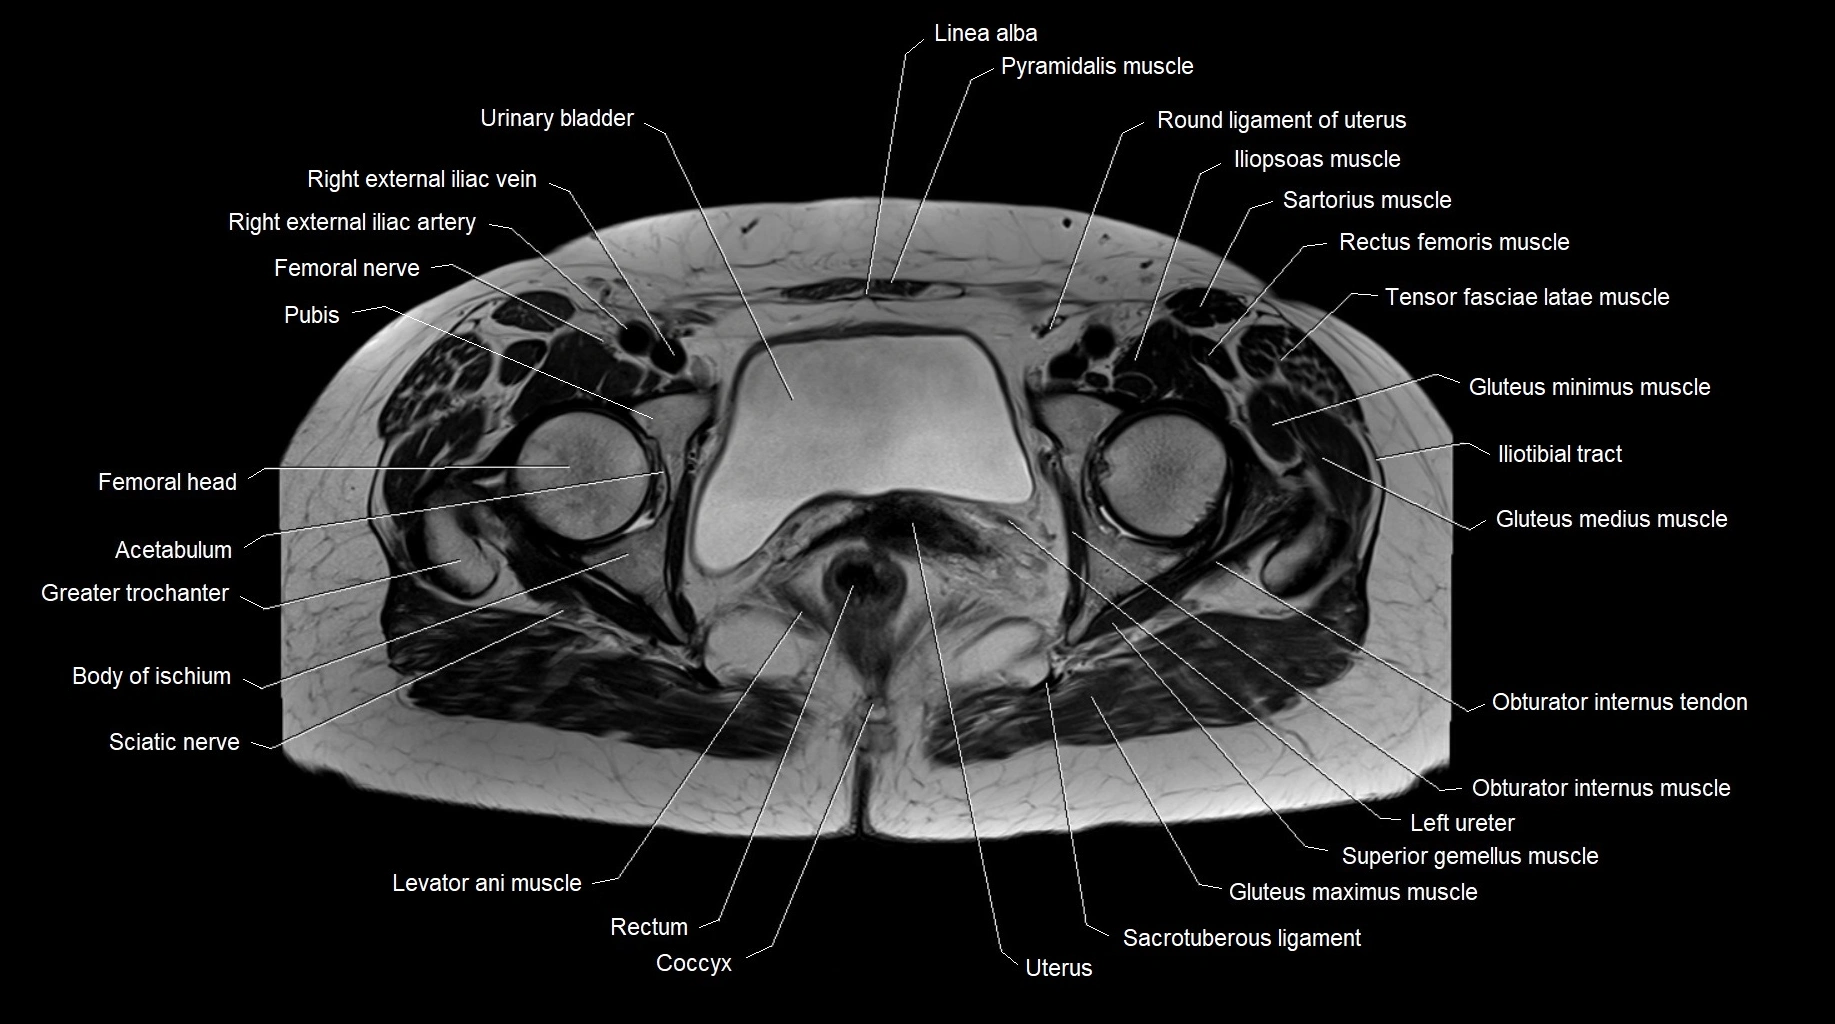

MRI images